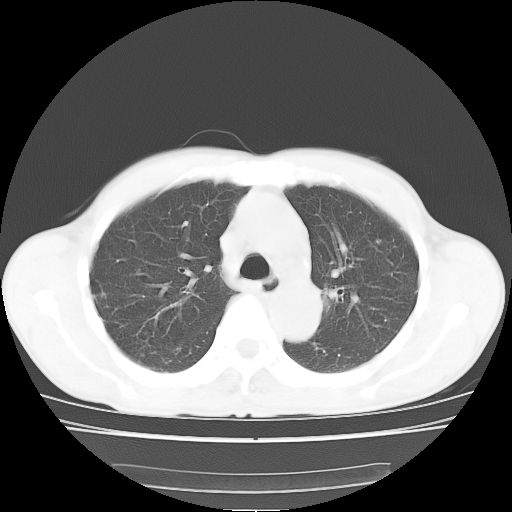

标题: CT25795:感冒后反复咳嗽两月余,痰中带血半月余。X诊断“肺 [打印本页]

标题: CT25795:感冒后反复咳嗽两月余,痰中带血半月余。X诊断“肺

1.双肺肺梗塞(理由:病灶呈三角形,与胸膜相连且局部胸膜肥厚,左心室增大)伴肺感染。

2.一元论双肺感染。

肺梗塞虽然有创意,但不现实。我考虑感染性病灶。

考虑两肺感染性病变,左肺上叶舌段肿瘤性病变待排;建议抗炎治疗后复查。